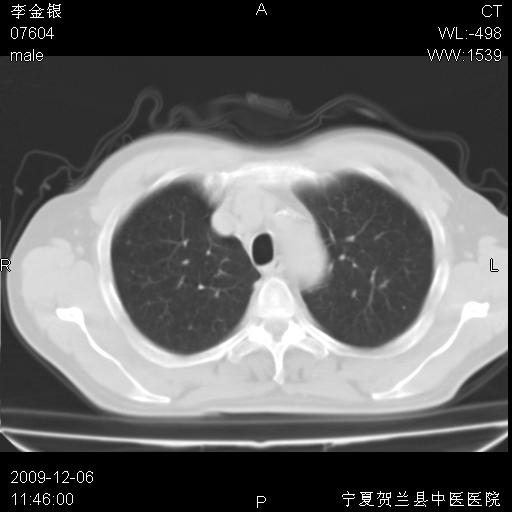

该病人 ,男,62岁,主因咳痰带血两天

考虑右肺中央型占位性病变并阻塞性肺炎.(右肺上叶支气管变窄),建议支纤镜检查.

支持右侧中央型肺癌伴上叶阻塞性炎症.

考虑右肺中心型肺癌伴阻塞性肺炎及右肺门淋巴结转移,建议纤维支气管镜进一步检查。

支气管壁明显增厚 管腔狭窄,腔静脉后多个淋巴肿大,结合年龄病史考虑右肺上叶中央型肺癌并阻塞性肺炎

右肺上叶后段支气管阻塞,右上肺门占位,相应肺段阻塞性肺炎,右肺门有淋巴结肿大。诊断右肺上叶中心型肺癌,阻塞性肺肺炎、右肺门淋巴结转移。

考虑右侧中央型肺癌并阻塞性炎症及不张,建议ct增强!!